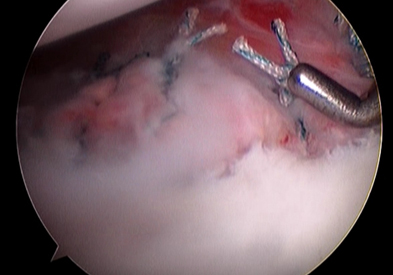

파열된 전방 관절순을 관절경하 봉합술을 시행 파열된 전방 관절순을 관절경하 봉합술을 시행

수술적 치료의 방법은 관절이 탈구될 때 발생한 관절와순을 봉합하는 수술을 시행할 수 있으며 (일명 “방카르트수술”) 과거에는 관절을 열어 노출 시킨 후에 봉합하는 방법을 많이 이용하였으나 현재는 대부분 관절경을 이용하여 복원술을 시행하며 이로 인해 회복이 빠르고 수술 시 발생할 수 있는 관절 손상의 가능성이 줄었습니다. 골결손이 심한 경우에는 이에 대해 골이식 등의 치료법을 이용할 수 있습니다.